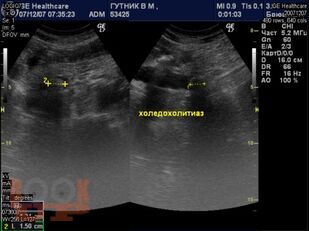

Диагностика и лечение механической желтухи

Учебно-методическое пособие посвящено актуальным проблемам этиологии, патогенеза, диагностики, современным методам консервативного и оперативного лечения механической желтухи. Представлены новые классификации, схемы консервативного лечения, современные виды оперативного лечения, учитывая утвержденные клинические рекомендации Российского общества хирургов (2018 г.). Издание иллюстрировано рисунками, таблицами, имеются тестовые задания и задачи. Пособие предназначено для слушателей дополнительного профессионального образования и ординаторов, обучающихся по специальности 31.08.67 Хирургия.